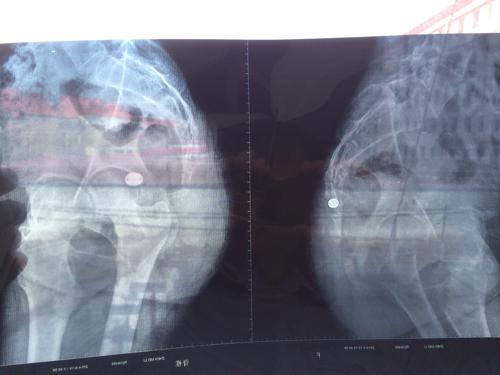

问:尾椎骨受伤,这是拍的x片,请帮忙看下严不严重?

我女朋友前两天尾椎骨摔疼了,照了片,麻烦

正常骶尾骨x线图片

正常尾椎骨x光片

正常人尾椎骨x光片图

人正常尾骨x光图